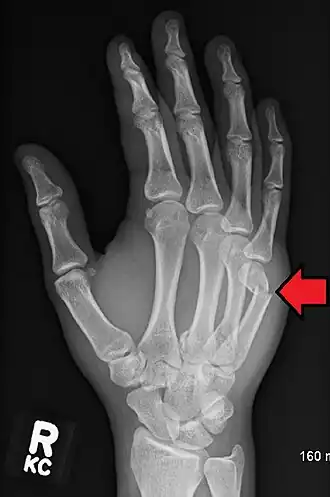

| Apresentação de uma fratura da cabeça do quinto metacarpo | |

A fratura de um boxeador é a fratura do quinto osso metacarpo da mão, próximo à articulação do dedo. Ocasionalmente, também é usado para se referir a fraturas do quarto metacarpo. Os sintomas incluem dor e articulação dos dedos deprimida. Classicamente, ocorre depois que uma pessoa atinge um objeto com o punho fechado. A junta é então dobrada em direção à palma da mão.[1] O diagnóstico geralmente é suspeitado com base nos sintomas e confirmado com raios-X.[1]

O diagnóstico por exame médico é o mais comum, geralmente confirmado por raios X. O raio X é usado para mostrar a fratura e suas angulações. Uma tomografia computadorizada pode ser feita em casos muito raros para fornecer uma imagem mais detalhada.[5]